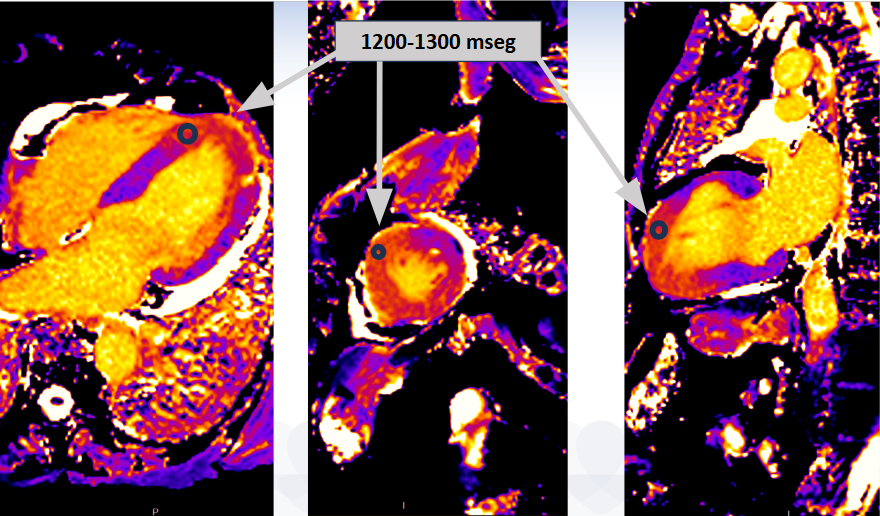

The MRI showed preserved biventricular systolic function, with increased wall thickness in the apical and basal anteroseptal segments (15 mm), with preserved motion. There was diffuse late gadolinium enhancement in the apical segments, with a non-ischemic necrotic pattern; increased T1 and T2 mapping times at the apical level. The findings were reinterpreted as possible apical hypertrophic cardiomyopathy with intramyocardial gadolinium and edema in the apical segments, suggesting an active inflammatory process. It was recommended to repeat the study in 3-6 months to assess evolution.

MRI - T1 mapping: 4 chamber - short axis - 2 chamber

The MRI showed preserved biventricular systolic function, with increased wall thickness in the apical and basal anteroseptal segments (15 mm), with preserved motion. There was diffuse late gadolinium enhancement in the apical segments, with a non-ischemic necrotic pattern; increased T1 and T2 mapping times at the apical level. The findings were reinterpreted as possible apical hypertrophic cardiomyopathy with intramyocardial gadolinium and edema in the apical segments, suggesting an active inflammatory process. It was recommended to repeat the study in 3-6 months to assess evolution.

MRI - T1 mapping: 4 chamber - short axis - 2 chamber